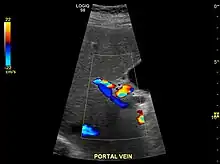

Hepatofugal (non-forward) flow in portal vein

Imaging

Ultrasound is routinely used in the evaluation of cirrhosis.[34] It may show a small and shrunken liver in advanced disease. On ultrasound, there is increased echogenicity with irregular appearing areas.[51] Other suggestive findings are an enlarged caudate lobe, widening of the fissures and enlargement of the spleen.[52] An enlarged spleen, which normally measures less than 11–12 cm (4.3–4.7 in) in adults, may suggest underlying portal hypertension.[53] Ultrasound may also screen for hepatocellular carcinoma and portal hypertension.[34] This is done by assessing flow in the hepatic vein.[54] An increased portal vein pulsatility may be seen. However, this may be a sign of elevated right atrial pressure.[55] Portal vein pulsatility are usually measured by a pulsatility indices (PI).[54] A number above a certain values indicates cirrhosis (see table below).